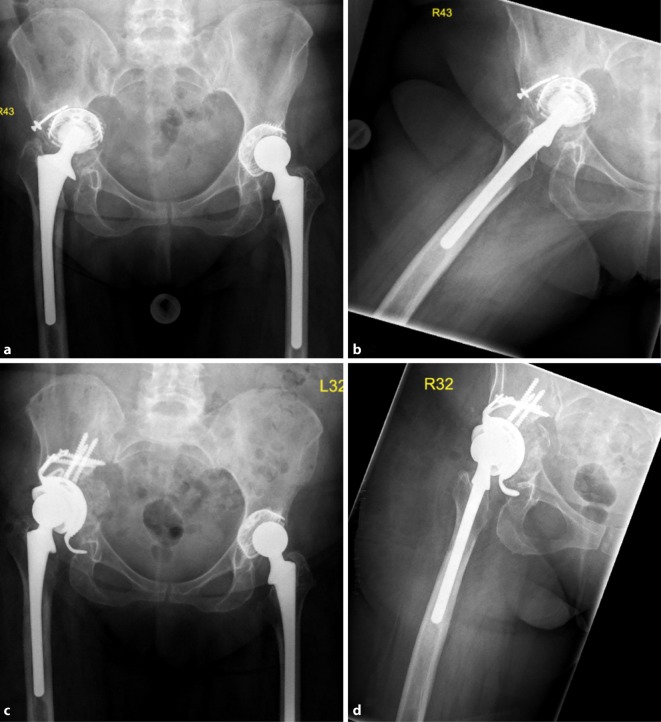

Fig. 5.

AP X‑ray of the hip (a) and axial view (b) of a 79-year-old male patient with cup loosening, type III acetabular bone defect; X‑ray of the hip AP (c) and axial (d) after treatment with an acetabular revision cup (cranial cup with an iliac stem and cranial strap) and allogenic cancellous bone (AQ Implants) (Courtesy of the Department of Diagnostic and Interventional Radiology, University Hospital of Leipzig, all rights reserved)